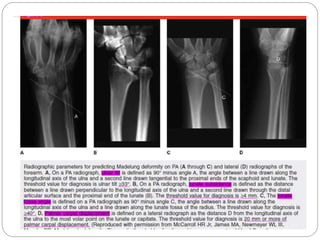

These are the radiographs of another

patient with the same condition

 Describe the radiographs

 AP and lat x ray of wrist

 Ap view

 Posetive ulnar variance

 Significant

 ulnar tilt

 Lunate subsidence

 Lat view

 Palmar carpal displacement

McCarron et al

 4 radiographic parameters for early MD

 Ulnar tilt >330

 Lunate subsidence > 4mm

 Lunate fossa angle > 400

 Palmar carpal displacement > 20mm